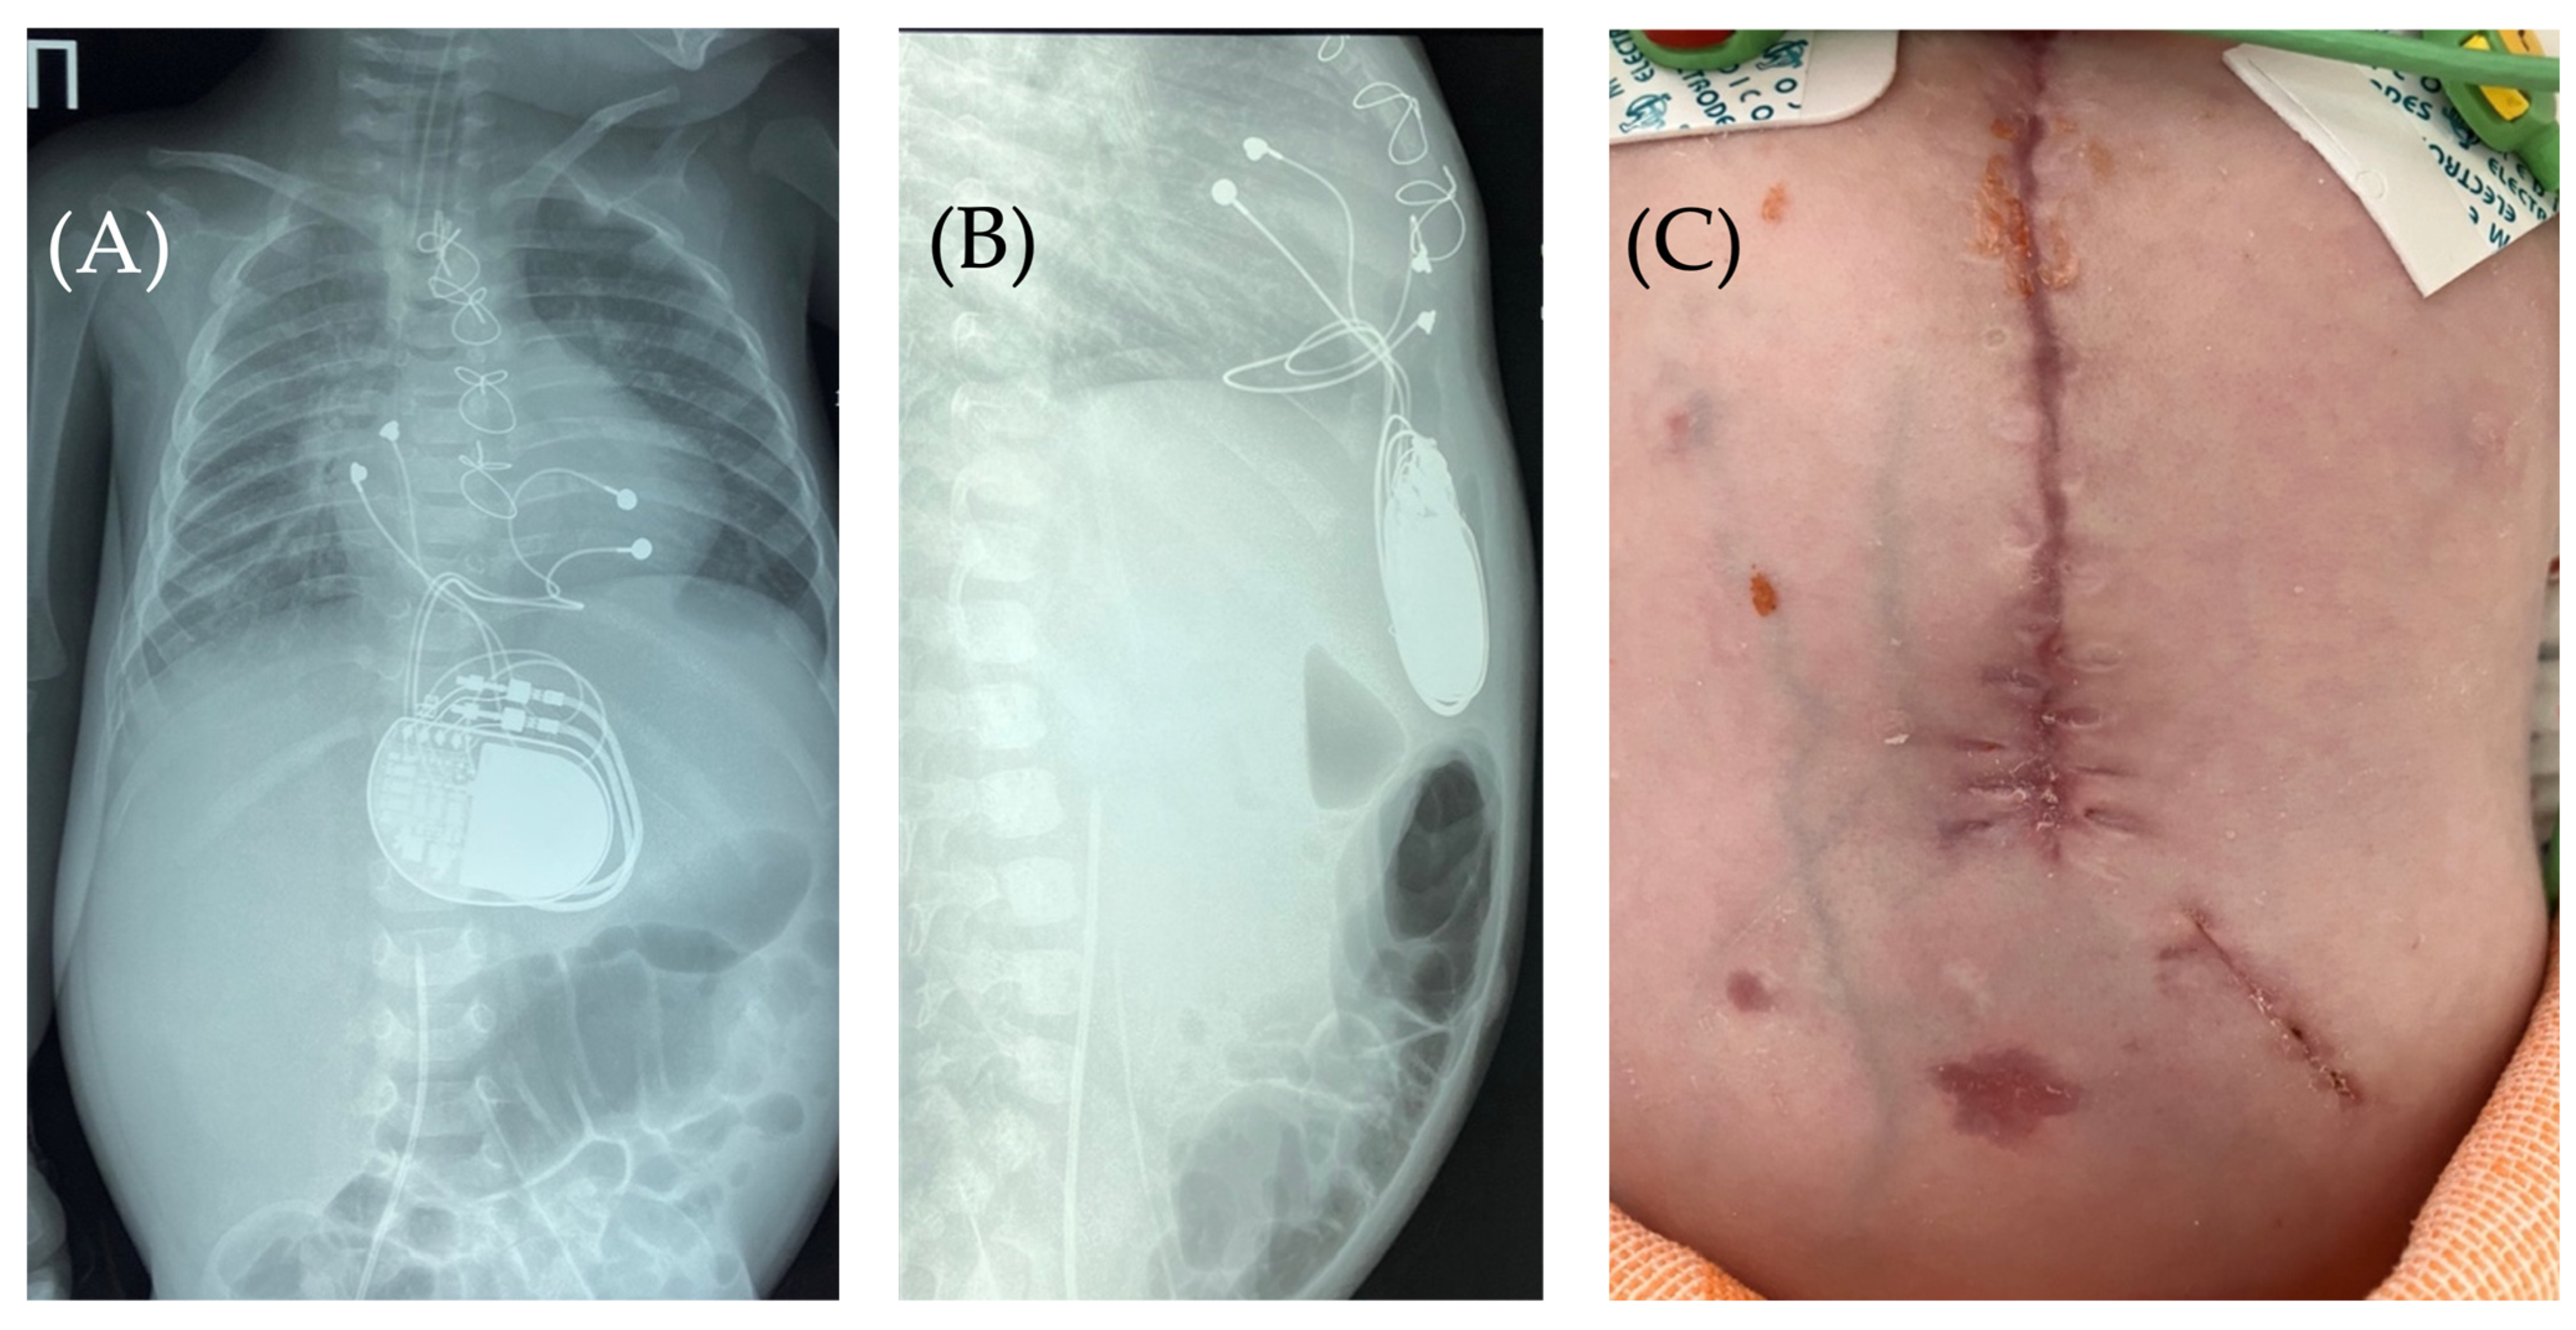

On the 8th postoperative day, the wound healed by primary intention. During pacing programming, impedance values, atrial and ventricular pacing thresholds were satisfactory; no pacing abnormalities were detected. On the 10th postoperative day, local examination in the upper anterior abdominal wall along the midline revealed a localized bulge of skin and soft tissue in the projection of the pacemaker pocket (Figure 1).

The skin in the area of the abdominal wall soft tissue bulge had normal color and temperature. Palpation revealed soft tissue with no detectable fluctuations. The pacemaker pocket was palpated within its bed. To rule out pneumothorax and perforation of a hollow abdominal organ, chest and abdominal radiography and fluoroscopy were performed, as well as GI contrast imaging (Figure 2 and Figure 3).

Figure 1. Thoracoabdominal view. Lateral (A) and frontal (B) views. A mass and soft tissue bulge are noted (red arrow) in the area of the pacemaker pocket in the subxiphoid region of the anterior abdominal wall, limited by the projection of the pacemaker body.